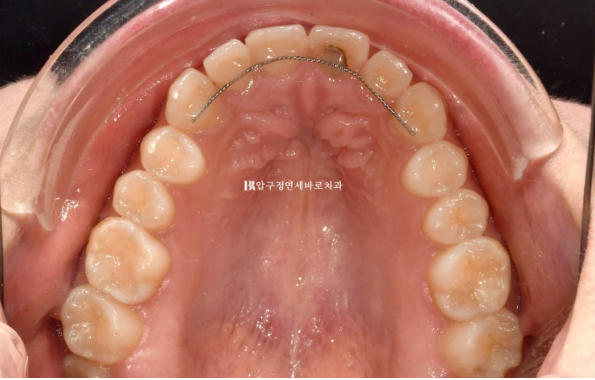

Let’s compare occlusal surface photos so you can get a sense of how thin Gelami is.

The image above is the initial visit, and the one below shows all 8 teeth fitted with no-prep laminates without any removal.

The fact that there is no noticeable difference in thickness shows how thin Gelami is.

At the thinnest point, it can be reproduced down to 0.1 mm.